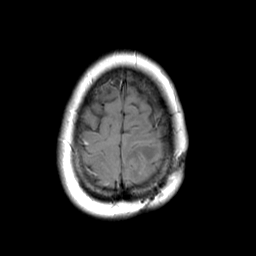

MR Study #3 -- Slice #45